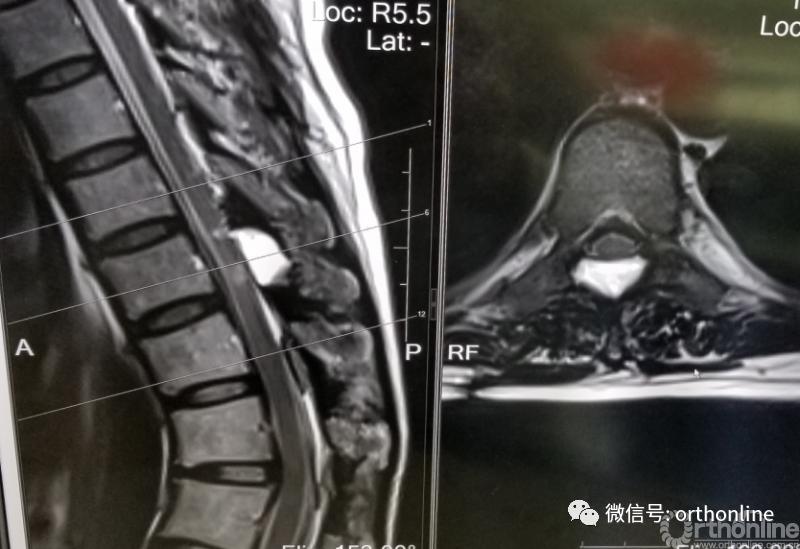

脊柱内镜手术通常作为首选手术方法,能有效地减压并进行相应的处理。适用于胸椎管狭窄症,如胸椎黄韧带肥厚症、胸椎间盘突出症、胸椎后纵韧带骨化症等,尤其适合单节段狭窄者。

二、选择性适应证

脊柱内镜作为可供选择的手术方法主要用于以下情况:

1.胸椎结核:在脊柱内镜下进行穿刺及置管引流等;

2.胸椎椎管内囊肿:在脊柱内镜下进行病病灶切除术等;

3.胸椎后纵韧带骨化、骨水泥渗漏等;